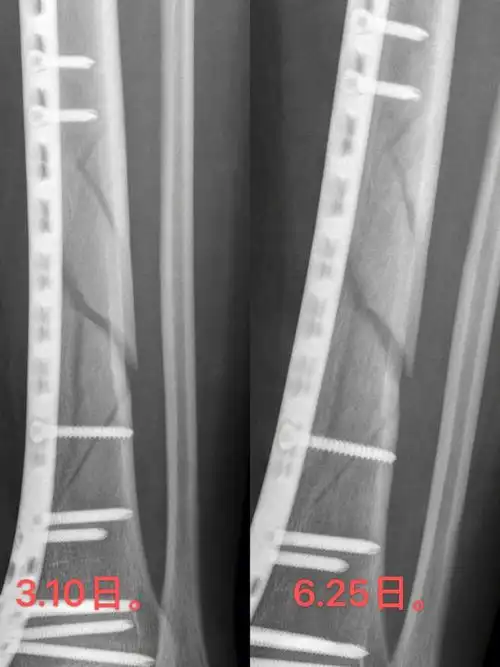

三踝骨折术后一个月复查

左胫骨下段螺旋粉碎性骨折术后110天